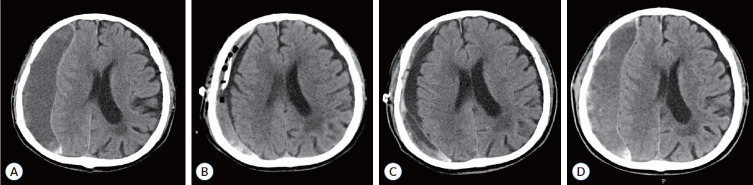

Methods: A total of 173 patients with CSDH who were hospitalized in our hospital from January 2018 to August 2023 were selected . All the patients underwent magnetic resonance imaging (MRI) examinations before surgery. According to whether patients with CSDH have relapsed after surgery, the patients are divided into recurrence group and non-recurrence group. FireVoxel software (https://firevoxel.org) was used to manually delineate the region of interest on the largest level of the hematoma cavity during MRI plain scans and measure the texture parameters. The texture parameters with statistical difference were analyzed by receiver operating characteristic curve.

Results: Heterogeneity and entropy texture parameters in the recurrence group were statistically different from those in the nonrecurrence group (p<0.05). When the cut-off point of the heterogeneity parameter was 0.284, the sensitivity, specificity, and accuracy of judging whether CSDH relapsed were 83.3%, 80.4%, and 80.7%, respectively.